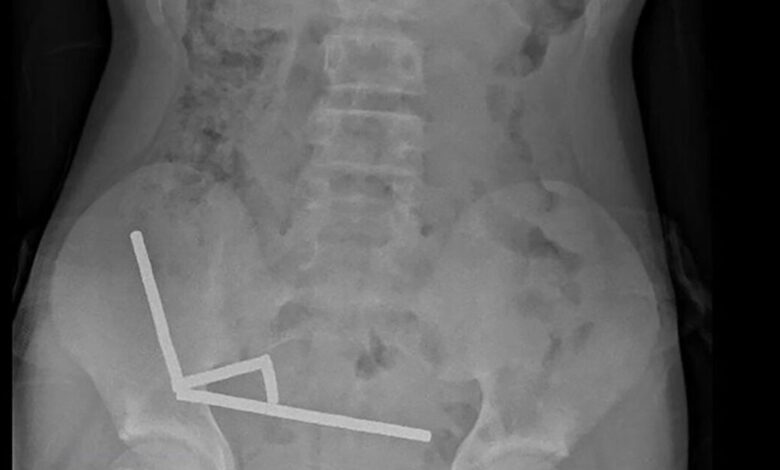

Η ακτινογραφία έδειξε ότι οι μαγνήτες είχαν συγκεντρωθεί σε τέσσερις ευθείες γραμμές μέσα στα έντερα του παιδιού, όπως φάνηκε και στην ακτινογραφία.

«Φαινόταν ότι βρίσκονταν σε διαφορετικά σημεία του εντέρου, τα οποία είχαν κολλήσει μεταξύ τους λόγω των μαγνητικών δυνάμεων», αναφέρει η έκθεση.